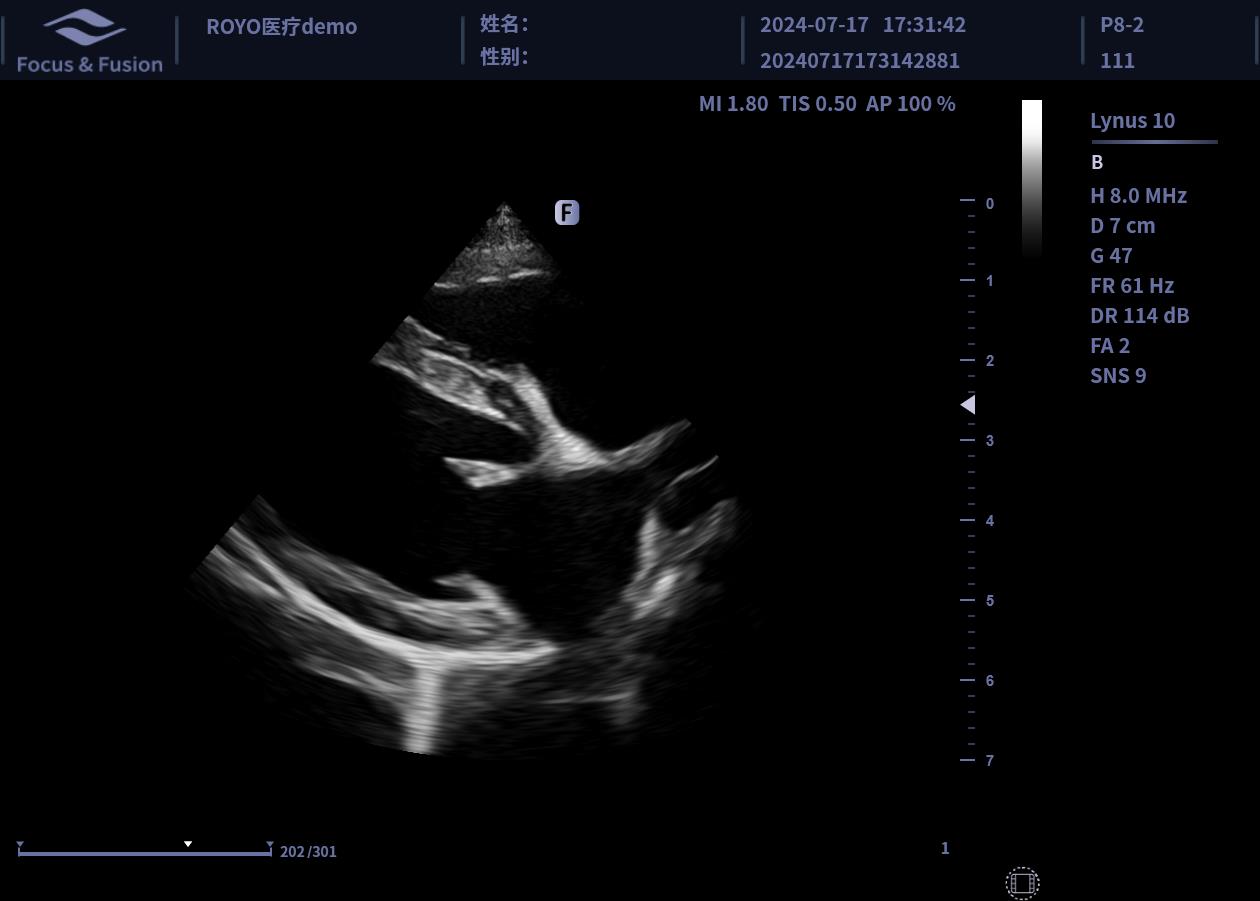

圖片展示

Image List